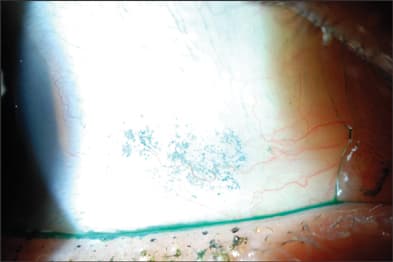

Lissamine green staining revealed mild dry eye that required pretreatment to achieve optimal results.